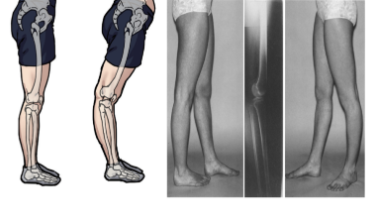

4.발목 변형과 다리 안쪽 회전의 관계

발목의 변형은 비록 흔한 현상은 아니지만,

다리가 안쪽으로 회전되는 원인이 될 수 있다.

발목 변형은 무릎의 교정과 보행 패턴에 중대한 영향을 미칠 수 있다.

1. 발목 변형과 보행 패턴의 관계

- 발목의 변형과 보행 패턴은 서로 깊이 연관되어 있다.

- 특히 O다리, X다리와 같은 무릎 변형과 밀접한 관계가 있다.

2.오다리 교정 시 발목 상태 고려

- 오다리 교정 시 발목의 상태도 주의 깊게 고려해야 한다.

- 발목 변형은 다리 회전과 보행 패턴에 영향을 미칠 수 있기 때문이다.

3. 종합적 접근 필요

- 오다리 교정 및 치료 시 뼈의 구조적 문제뿐만 아니라

다리 회전, 근육 불균형, 발목 변형 등을 함께 고려해야 한다.

- 하나의 방법이나 원인만으로는 결과를 유추할 수 없으며,

모든 경우의 수를 열어두고 개선 방법을 찾아야 한다.